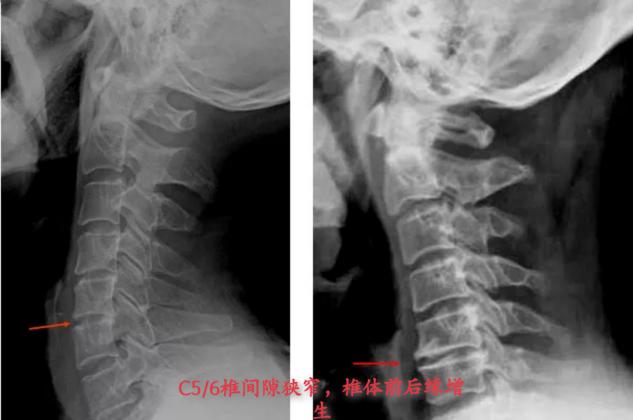

从X光片可看到骨质增生侵入椎管、椎间孔、横突孔;椎间隙变窄等。与临床症状的定位相一致。

从X光可看到脊椎连线异常:生理曲度改变,椎体滑脱等、脊柱侧弯、棘突偏歪等。以上描述与临床症状的定位诊断不一致。